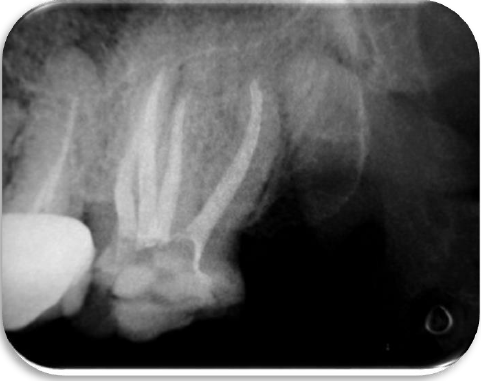

Se estableció la conductometría real de los cuatro conductos usando el localizador electrónico de forámenes apicales Root Zx II J. Morita. (MFG Corp, Japan) así como la verificación radiográfica. (Fig. 3 A, B) En este punto podemos clasificar el diente con dos conductos vestubulares uno MV y DV y dos conductos palatinos MP y DP.

Se realizó protocolo final de irrigación con Hipoclorito de Sodio al 5.25 % activándolo con el ultrasonido (NSK Varios 370, Japan) y la punta #30 del Endo Kit E12 (NSK, Japan). La obturación se realizó utilizando cemento sellador Sealepex (SybronEndo Kavo Kerr, USA) con técnica lateral modificada con ultrasonido (NSK Varios 370, Japan) y la punta #30 del Endo Kit E12 (NSK, Japón) (Figuras 4 y 5).